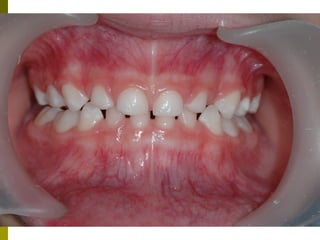

Πρώτη σχολική ηλικία 6-10 ετών

   Αρχίζει αλλαγή των τομέων και η ανατολή των

πρώτων μόνιμων γομφίων (μεικτή οδοντοφυΐα)

   Παρατηρούμε η αλλαγή δοντιών να γίνεται με τη

σωστή σειρά και στη σωστή θέση

   Μπορεί να χρειαστεί πρώιμη ορθοδοντική

θεραπεία, για να αποφευχθούν πιο δύσκολες και

πολύπλοκες εργασίες αργότερα

   Διατήρηση νεογιλών δοντιών στον οδοντικό

φραγμό μέχρι τη φυσιολογική τους απόπτωση